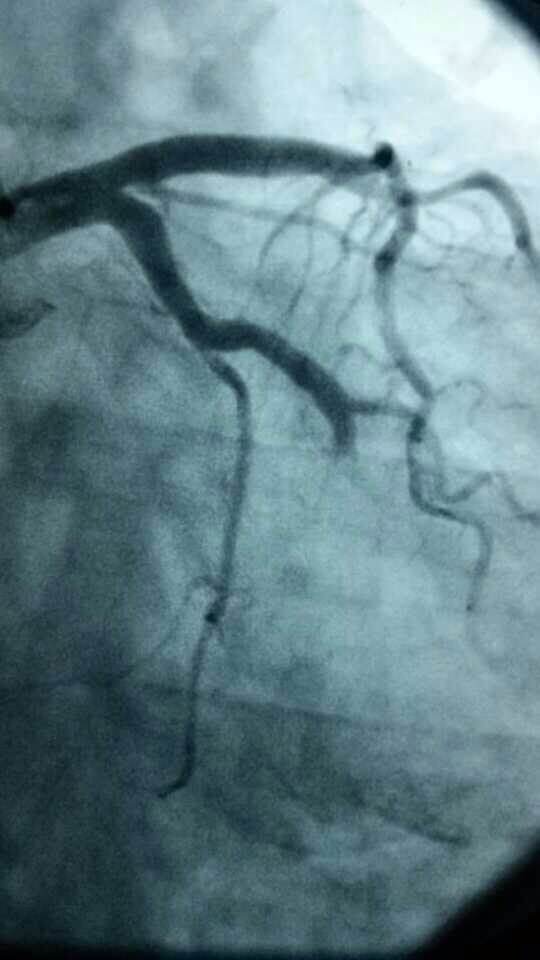

心内科医务人员在崔勇主任的带领下,蔡亚滨、林福根、雷建林、陈明辉、何晓、李仲伟等抢救团队连续奋战 8个小时成功抢救3名心梗患者。虽然工作艰辛,但接诊的三位病人都能转危为安,对医生来讲是最大的安慰。

专家提示:我国心血管病的发病率和死亡率常年居高不下,还出现明显年轻化趋势,白领、公务员等群体英年猝死的新闻屡见不鲜。在已经救治的近200例胸痛患者中,80%以上是急性冠状动脉综合征(这其中包含了心梗、不稳定心绞痛等)这类急性危险的病症,专家建议,40岁以上的人群,胸闷、胸痛突然发作,尤其是劳累后发作,或者一会儿痛一会儿不痛的要及时就诊。